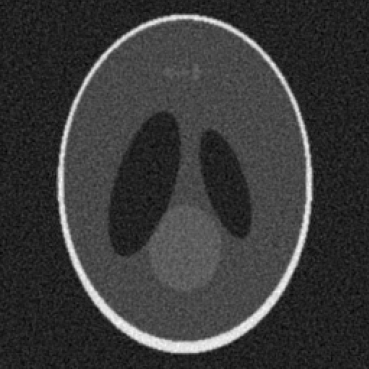

(c) Poisson Noise

(d) Gaussian Noise

Figure 1: Visualization of simulated artifacts with Shepp Logan Phantom.

Gaussian noise is introduced to model electronic and thermal variations that occur in acquisition hardware. This is achieved by sampling values from a normal distribution with a specified mean and standard deviation, then adding those samples to the sinogram. Gaussian noise is often useful in simulating readout errors and other consistent deviations in detector systems.

Ring artifacts result from defective or improperly calibrated detector elements. In the simulation, selected detector columns are set to zero or modified over a segment of the sinogram, which yields ring patterns when the volume is reconstructed. This allows algorithms to be tested on scenarios involving hardware disruption and calibration imbalances.